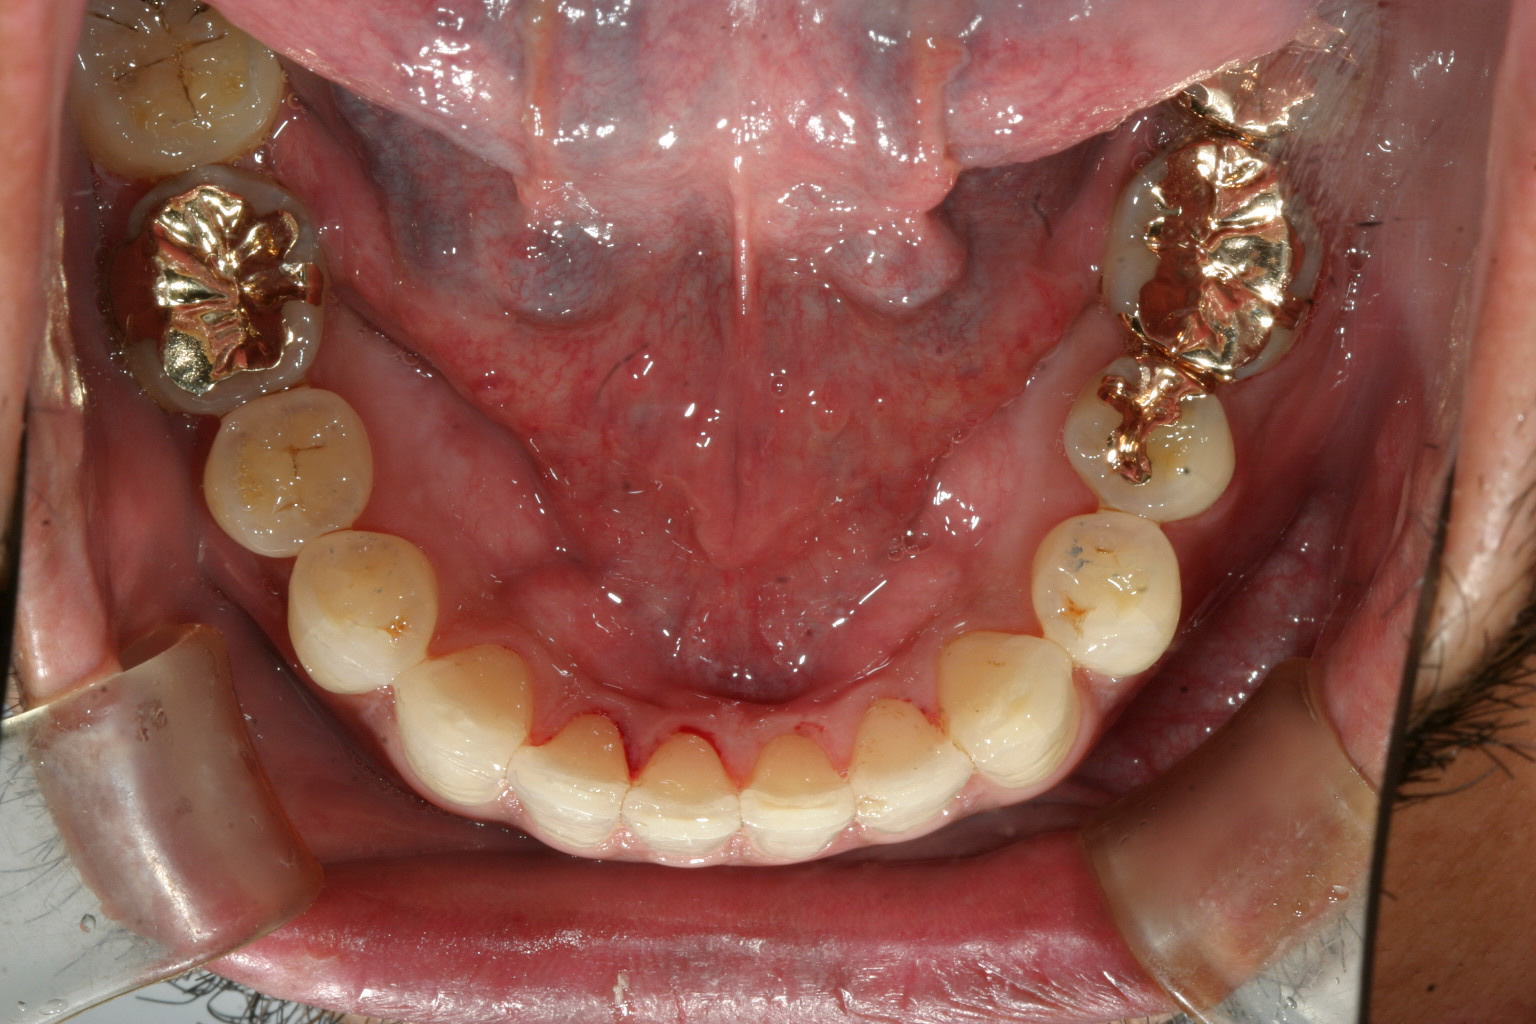

下顎前歯に少しガタガタが見受けられます。

インビザラインにて右側臼歯遠心移動(右側の大臼歯から順番に歯を後ろに下げて犬歯の入るスペースを確保する方法)